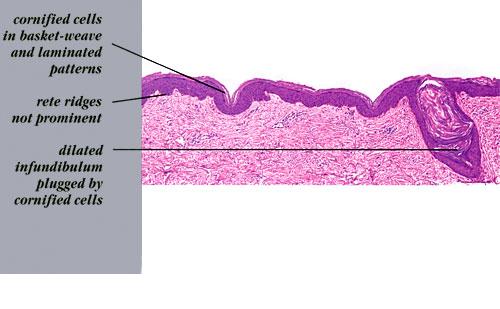

Histopathology.

The characteristic finding is the association of a moderate degree of hyperkeratosis with a thin or absent granular layer . The hyperkeratosis often extends into the hair follicles, resulting in large keratotic follicular plugs. The dermis is normal.